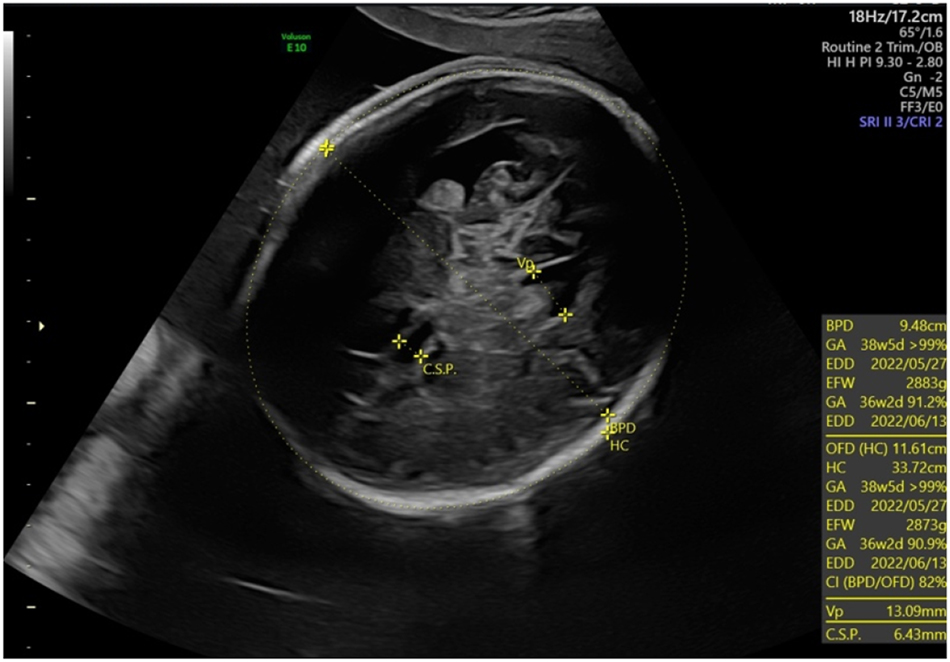

Macrocephaly (head circumference +3 SD) and ventriculomegaly (lateral ventricles 13 mm) for the fetus with cDM at 32 weeks.

Recent studies suggest that macrocephaly with or without borderline to mild ventriculomegaly in the third trimester may be a new sonographic finding associated with cDM, especially when head circumference was measured as normal on previous ultrasound examinations [19]. Regev et al. were the first to establish the association between neonatal mild ventriculomegaly and cDM [20]. Garcia-Alix A et al. reported the association of cDM with macrocephaly in ten of 14 newborns in 1991 [21]. Shinar et al. reported four cases of prenatal macrocephaly, two of which had mild ventriculomegaly. Prenatal macrocephaly is not secondary due to cerebral ventriculomegaly but may be due to prenatal megalocephaly caused an alteration in the DMPK gene [19].